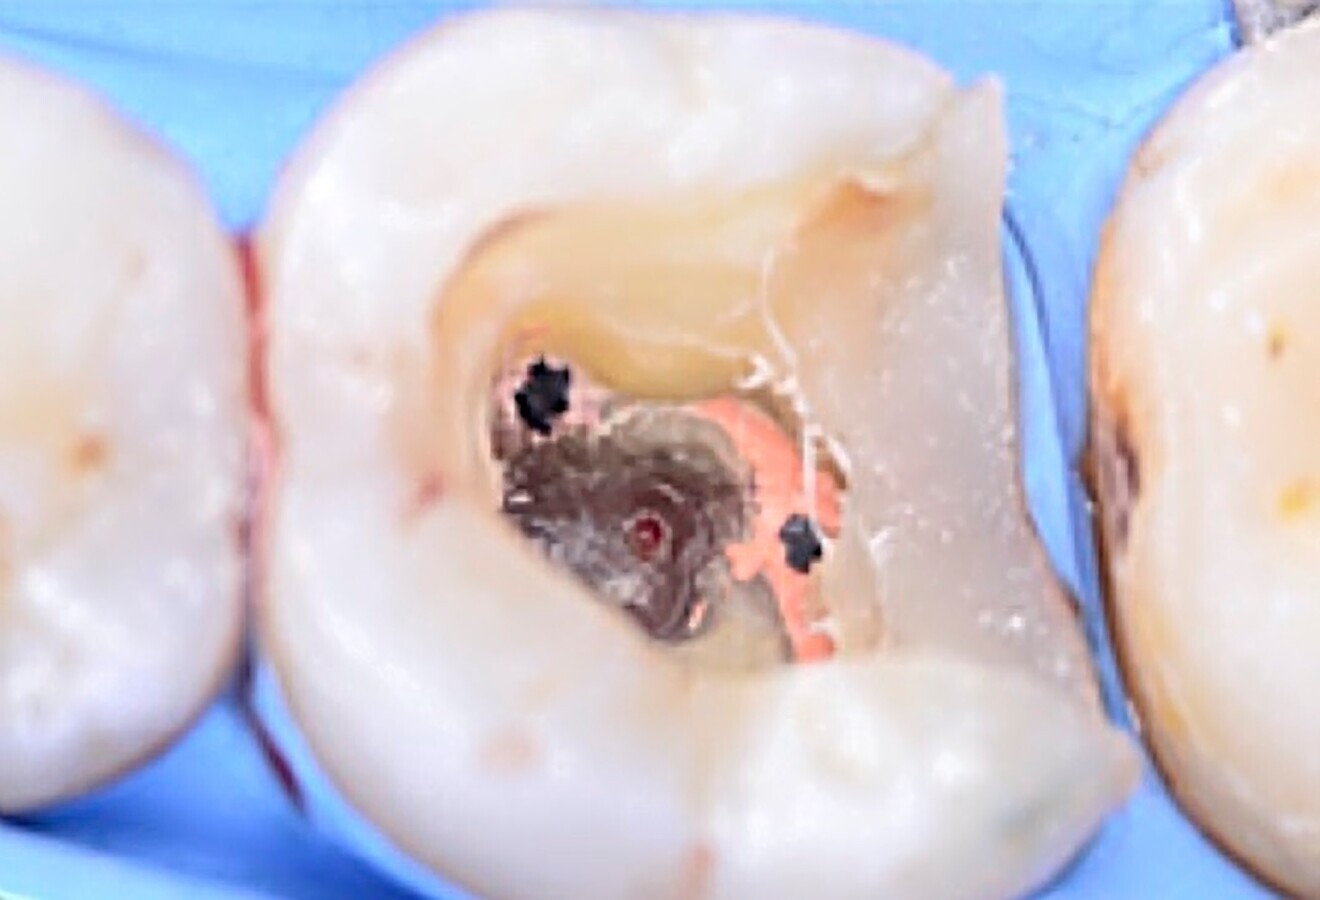

Fig. 5. Sellado de la perforación con Biodentine.

Fig. 6. Remoción de la gutapercha y localización de la longitud de trabajo.